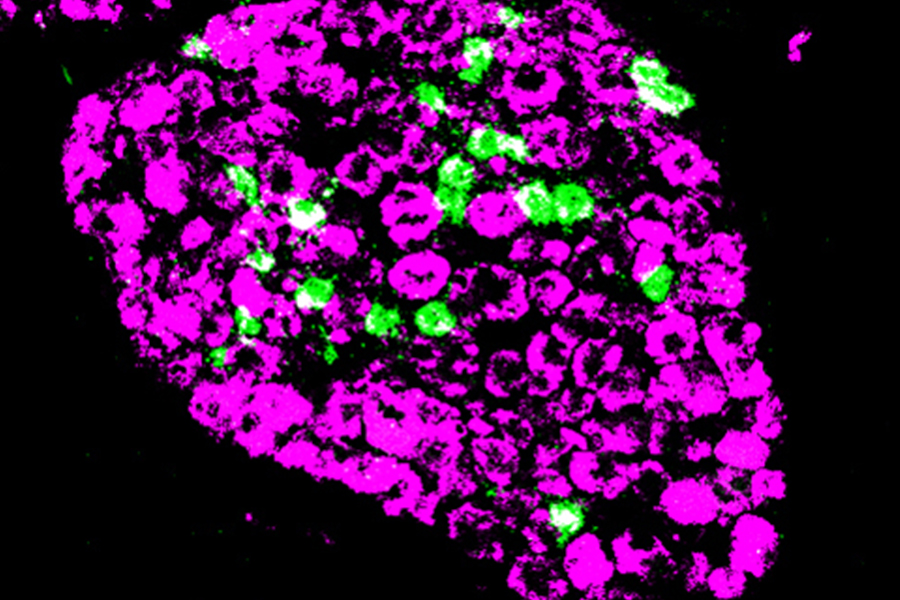

Tweaking T Cells to Treat Autoimmune Diseases

NIDCR intramural researcher Wanjun Chen, MD, and his colleagues used a novel immunotherapy to stimulate regulatory T cells to reprogram the immune systems of mice with experimental autoimmune encephalomyelitis, a disease model for multiple sclerosis. Their experiments, detailed in a recent paper in EBioMedicine, showed that the mice could be cured of disease and their immune tolerance restored.